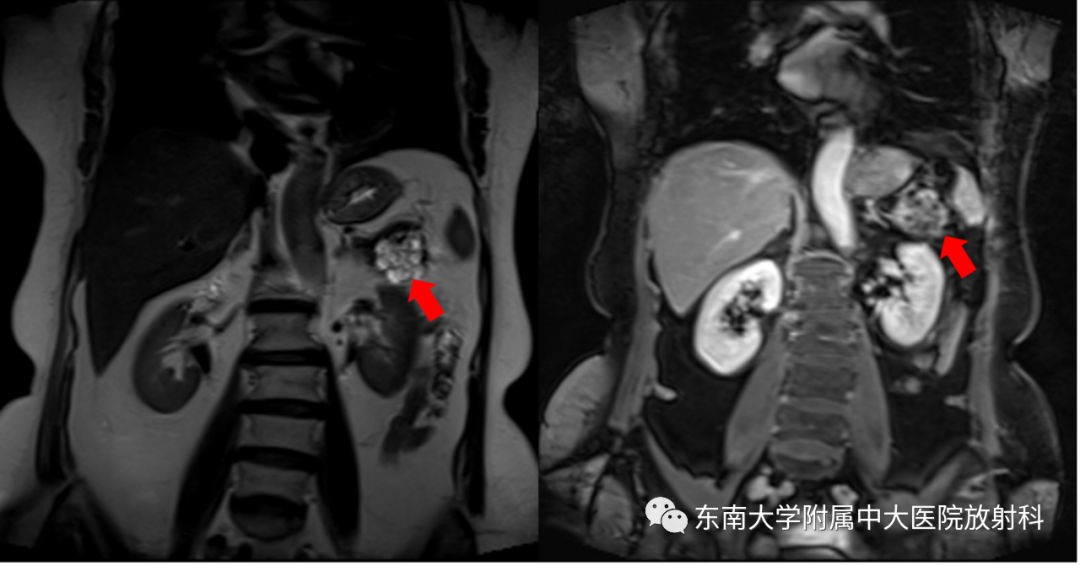

MRI平扫+增强